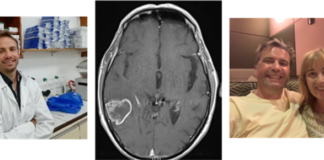

Super sponge’ innovation brings treatment hope to brain cancer patients

Scientists in Cardiff have been awarded a £500,000 grant to fund ground-breaking research which could bring much-needed hope to patients diagnosed with the most...